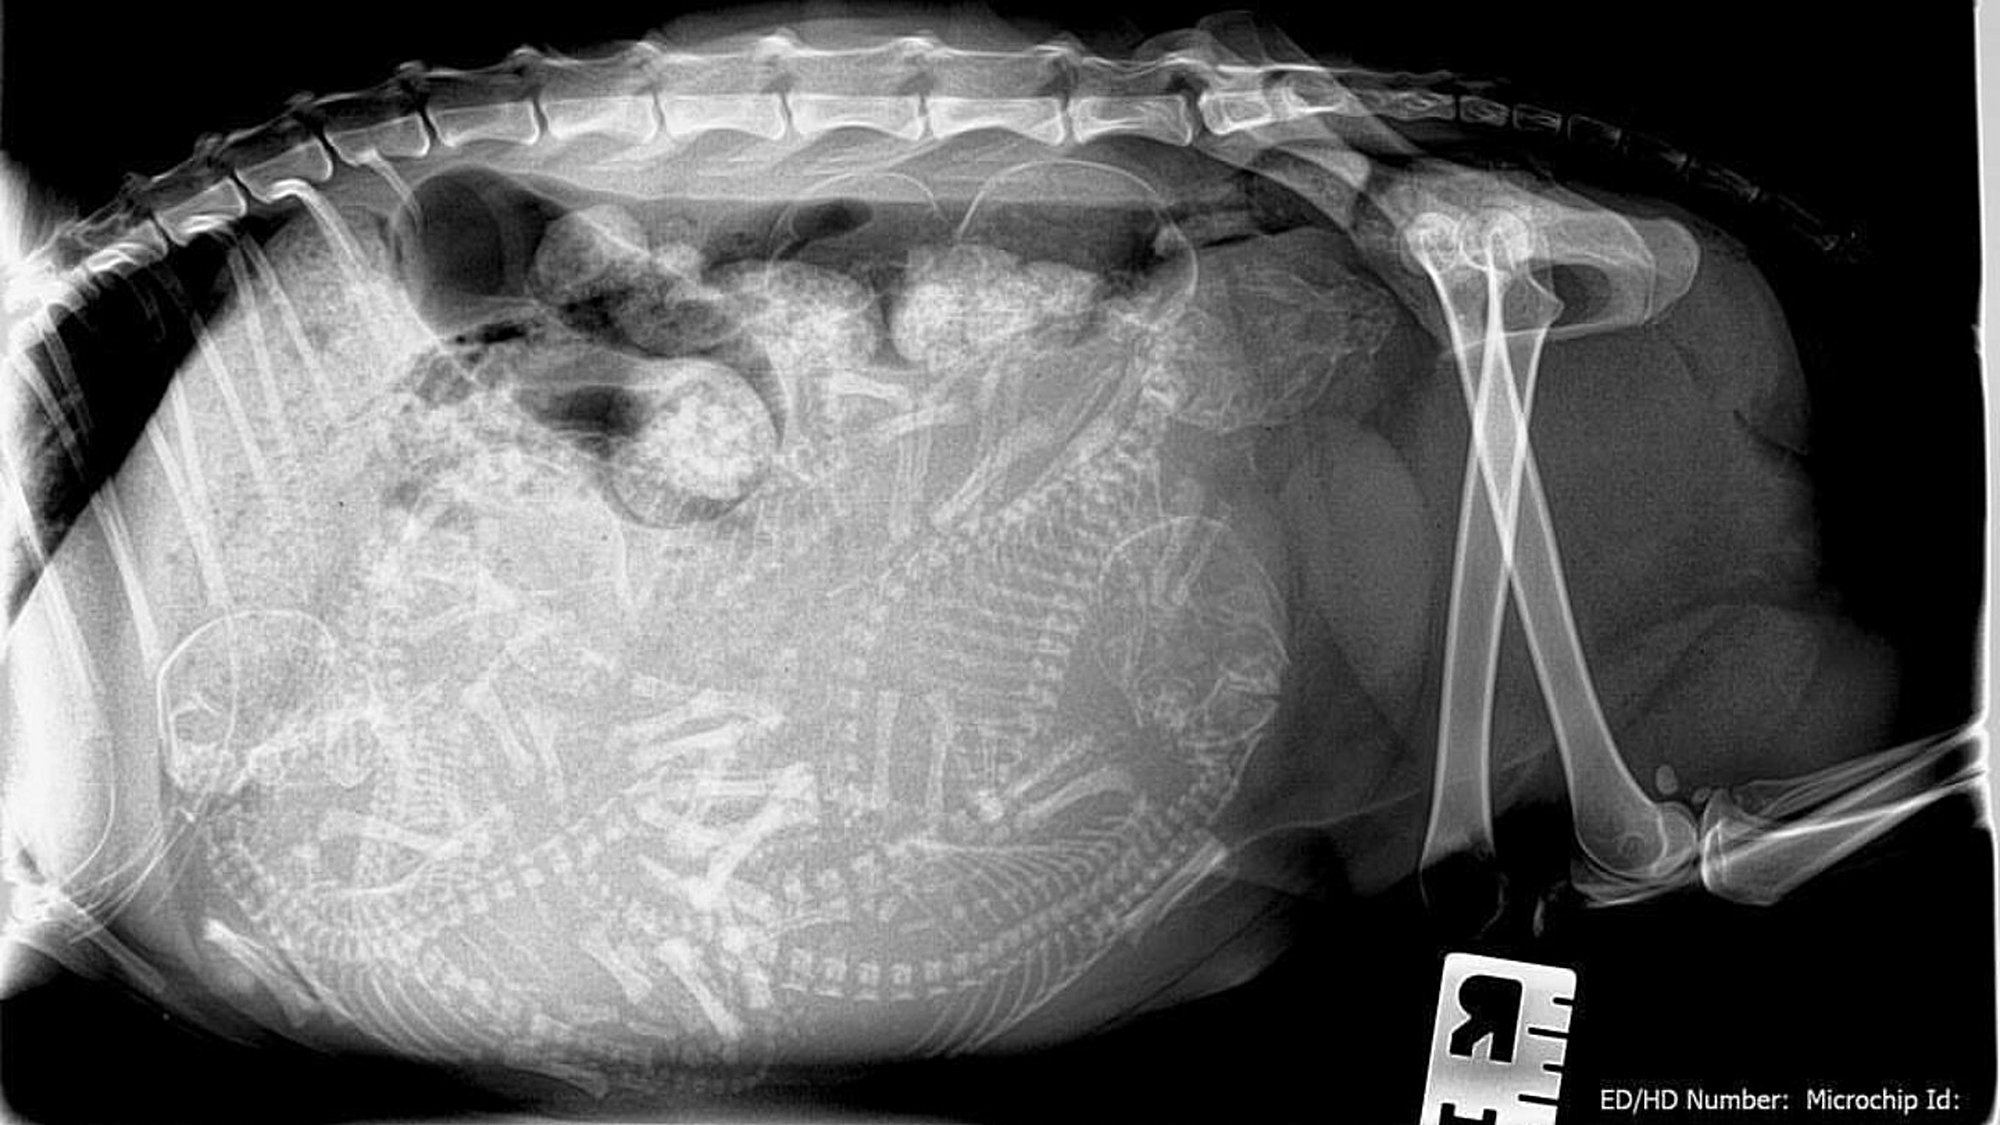

Aşağıda, muhteşem iki kare! Bu fotoğrafta üstte gördüğünüz görüntü, bir köpeğin hamileliği sırasında çekilmiş bir X-Işını taramasıdır. Alttaki ise, aynı durumdaki bir kediye aittir.

Bir kedi her gebelikte 1-8 yavruyu karnında taşıyabilir, yılda 2-3 kez hamile kalıp doğum yapabilir. Ömrü boyuncaysa bir dişi kedinin 100'ü aşkın yavrusu olabilir! Sadece bir çift kediden başlayarak, sadece 7 sene içerisinde ortalama 420.000 kedi doğması sağlanabilir! Köpeklerde de durum benzerdir.

Ortalamada bir köpek, hamileliği sırasında 1-10 arası yavruyu karnında taşıyabilir. Fakat köpekler genellikle biraz daha yavaş ürerler. Bu nedenle, sadece bir çift köpekle başladığınızda 6 sene içerisinde ortalamada 67.000 köpeğe ulaşabilirsiniz.